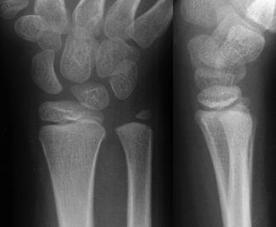

Largirea articulatiei scafo-lunare Fractura

Galeazzi

Semnul Terry Thomas

Fractura Galeazzi Fractura Monteggia